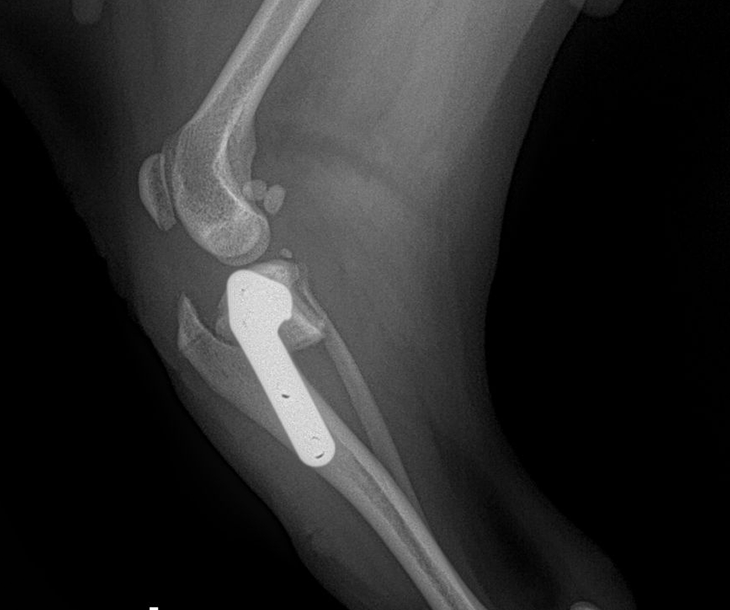

십자인대파열 절골술

십자인대 파열은 개의 무릎 관절에서 발생하는 일반적인 부상 중 하나로,특히 노령 개에서 더욱 흔하게 발생합니다.노화 과정은 십자인대의 결합 조직을 약화시켜, 일상 활동 중에도 파열이 발생할 수 있게 만듭니다. 이러한 상황은 관절의 안정성 손실,통증,그리고 장기적으로는 관절염으로 이어질 수 있는 심각한 문제를 초래합니다.